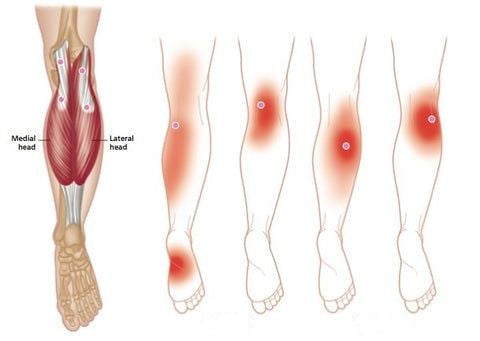

Μπορεί η γονάτη να χρησιμοποιηθεί όλη την ημέρα;

Ναι, χάρη στο αναπνεύσιμο ύφασμά της, είναι άνετη για να φοριέται όλη την ημέρα χωρίς ενοχλήσεις.

Είναι κατάλληλη για αθλητικές δραστηριότητες;

Ναι, προσφέρει εξαιρετική στήριξη για μέτριες δραστηριότητες, μειώνοντας παράλληλα τους κινδύνους τραυματισμού.

Είναι ρυθμιζόμενη η θερμότητα;

Όχι, η θερμότητα παράγεται φυσικά από τα σωματίδια του τουρμαλίνης σε επαφή με το δέρμα σας.